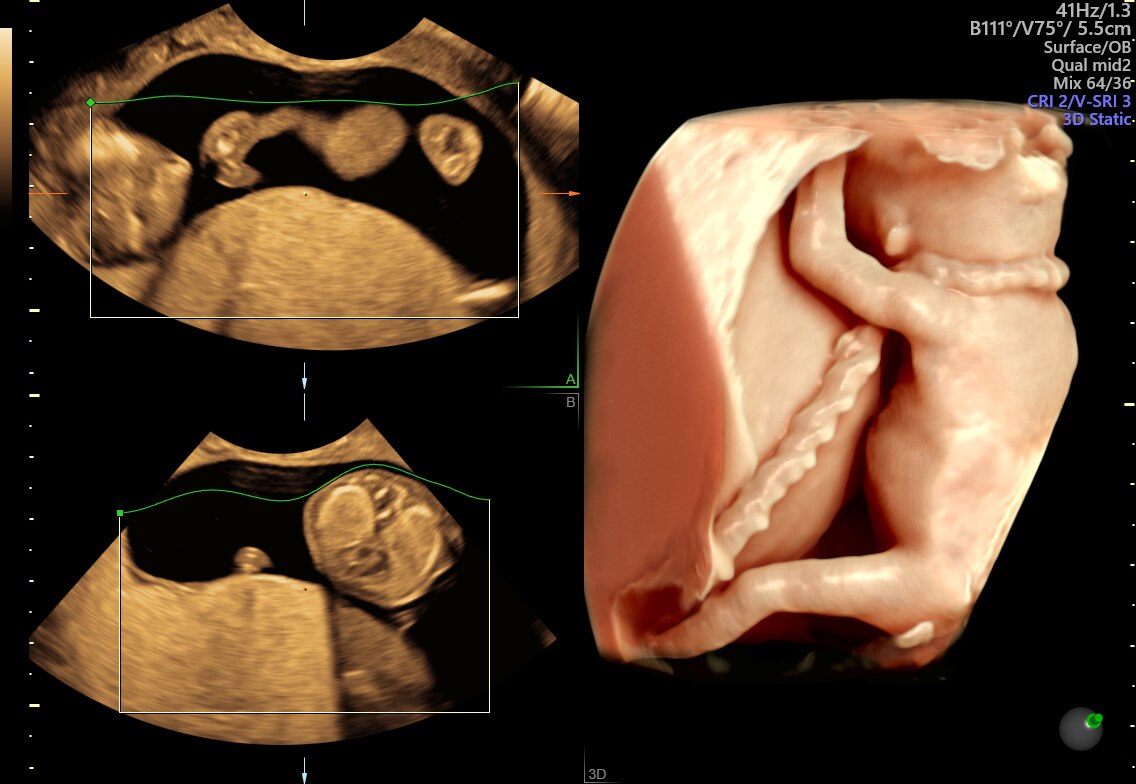

Fetus with HDlive™ generated with SonoRenderlive

HDlive Studio on a 10-week fetus